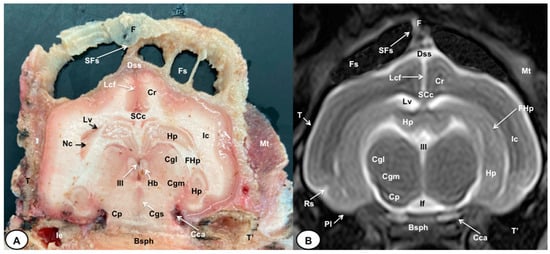

3.1. Anatomical Cross-Sections

3.2. Magnetic Resonance Imaging (MRI)